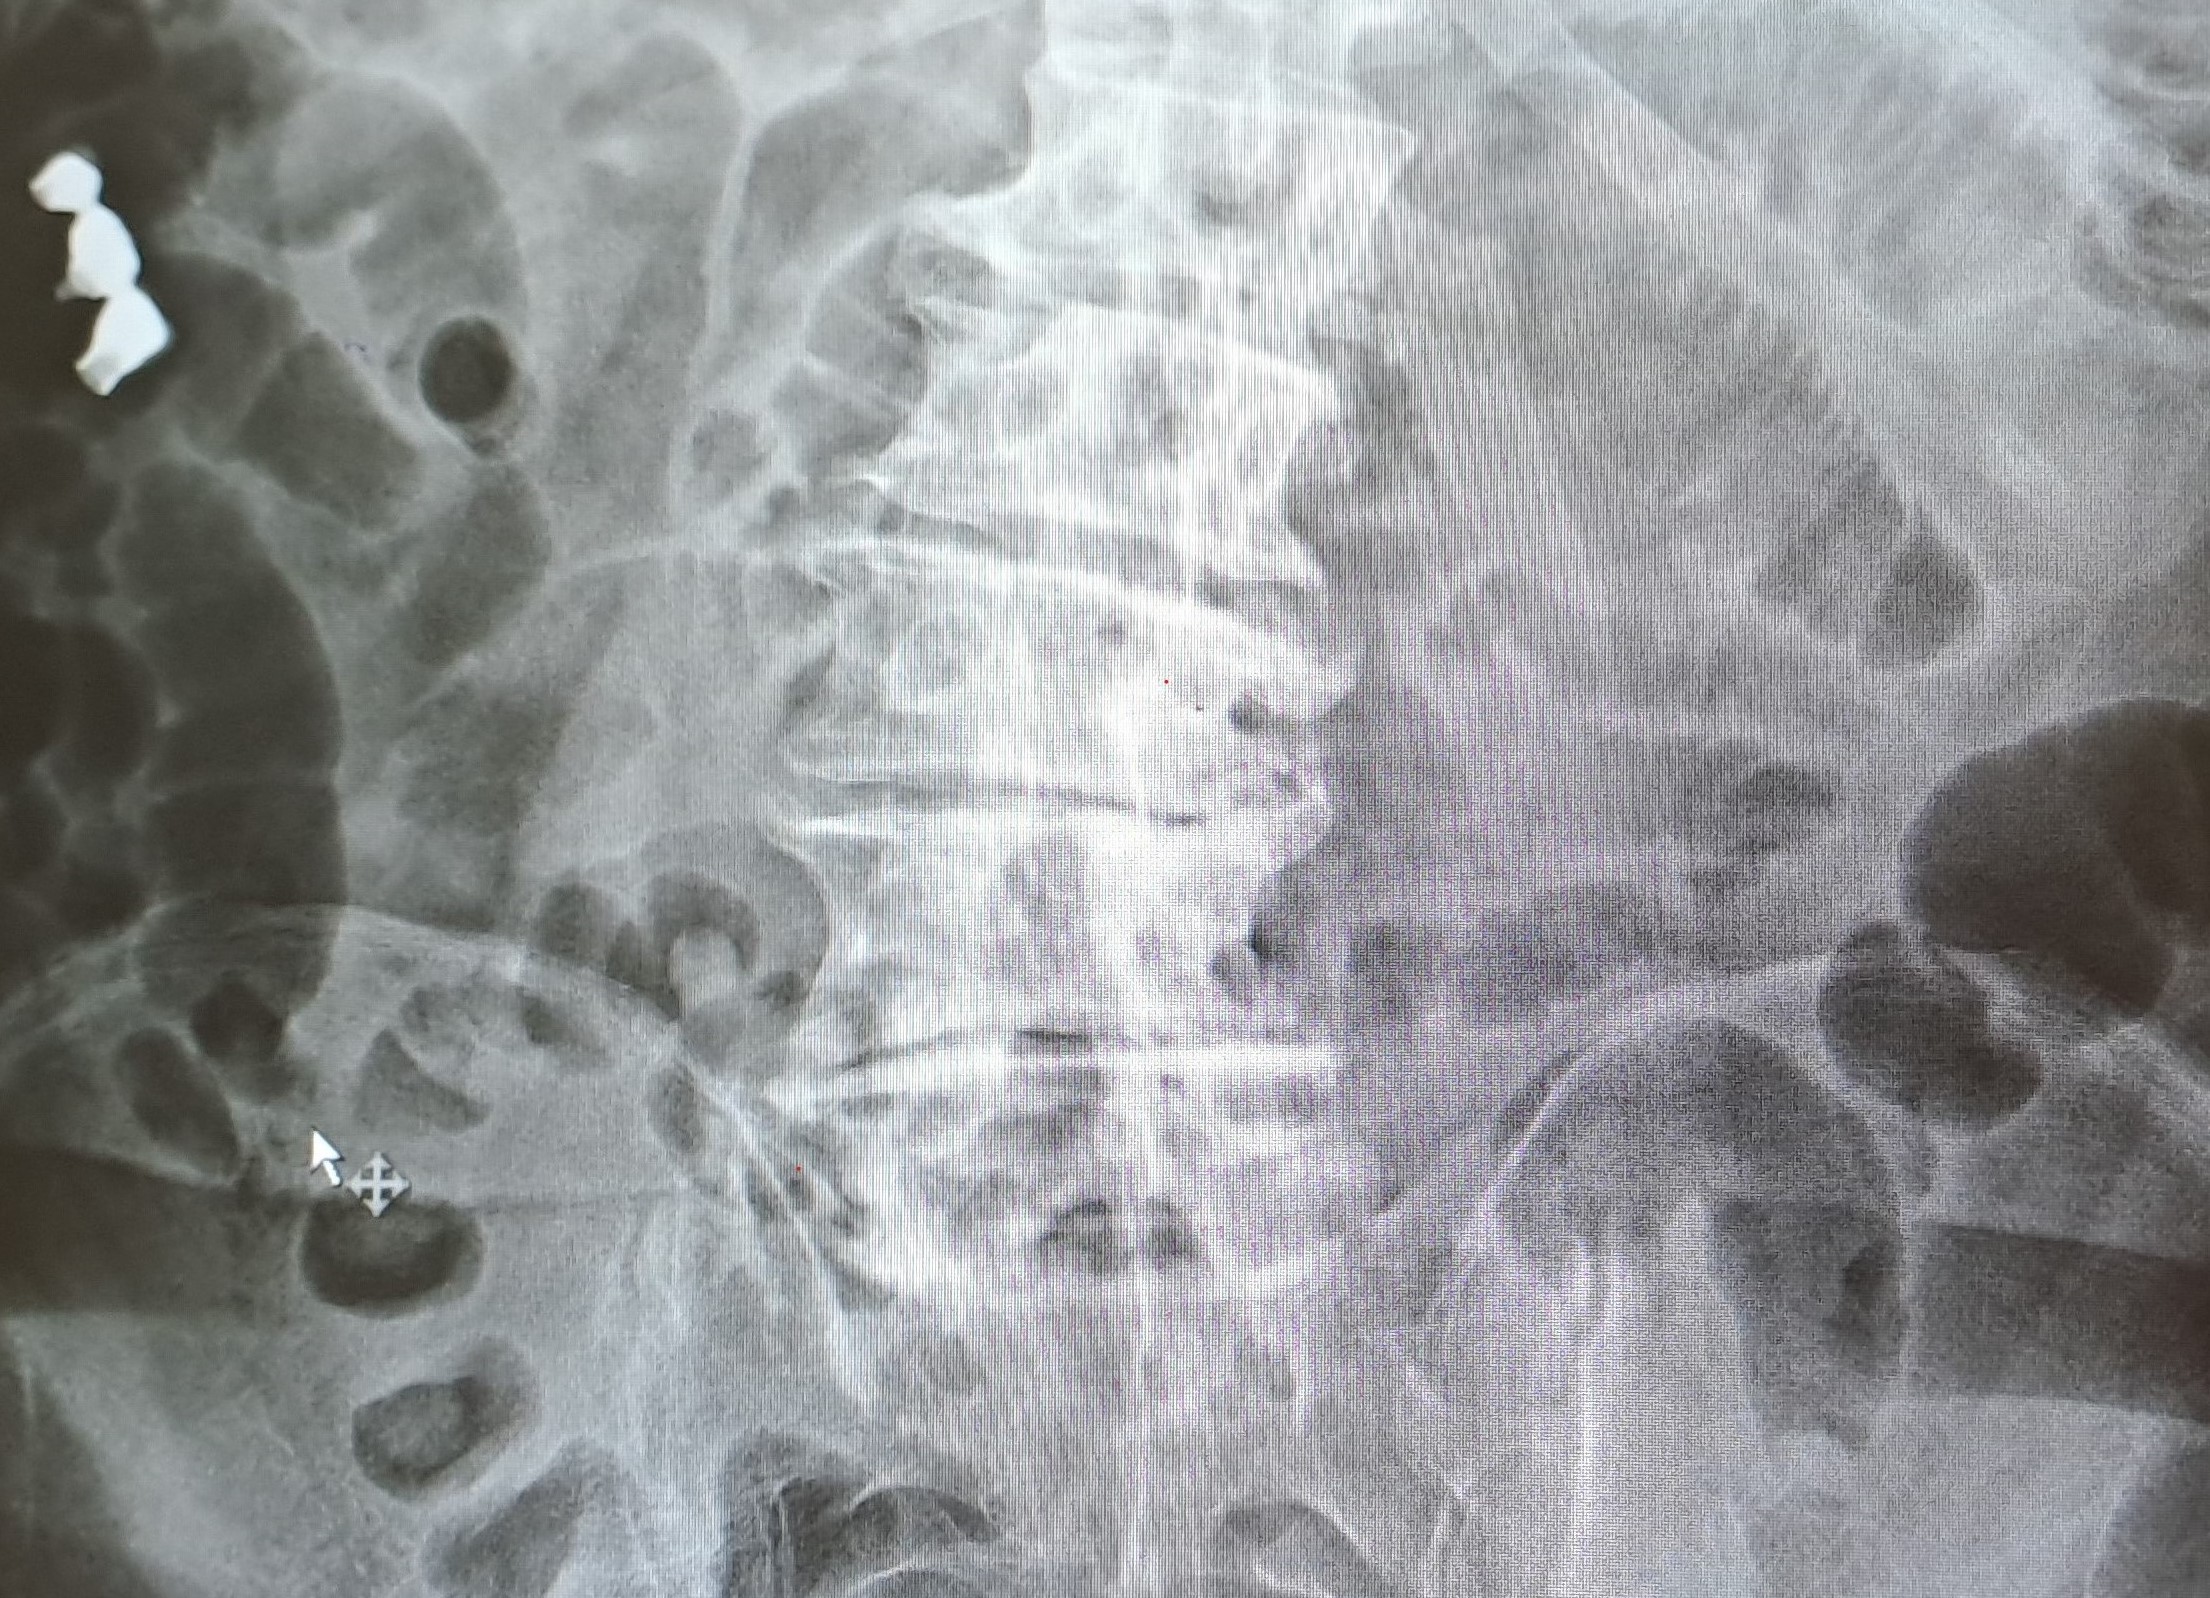

Hombre 63 años, no antecedentes médicos o quirúrgicos de interés. Acude por ingesta de prótesis dental hace 48 horas. Acudió al servicio de urgencias tras la ingesta siendo valorado con radiografías abdominales objetivando cuerpo extraño en hipocondrio izquierdo. Se realizó gastroscopia con sedación sin llegar a objetivar cuerpo extraño en estómago ni en porción proximal del duodeno, por lo que se realizó nueva radiografía abdominal de control al día siguiente objetivando cuerpo extraño en marco cólico derecho. Por lo que fue dado de alta con vigilancia de deposiciones. Refiere ausencia de visualización de la prótesis dental en las últimas deposiciones en el domicilio. Niega dolor abdominal, náuseas o vómito, no fiebre.

Repetimos radiografía sin objetivar cuerpo extraño, aunque no se visualiza ampolla rectal en la radiografía solicitada.